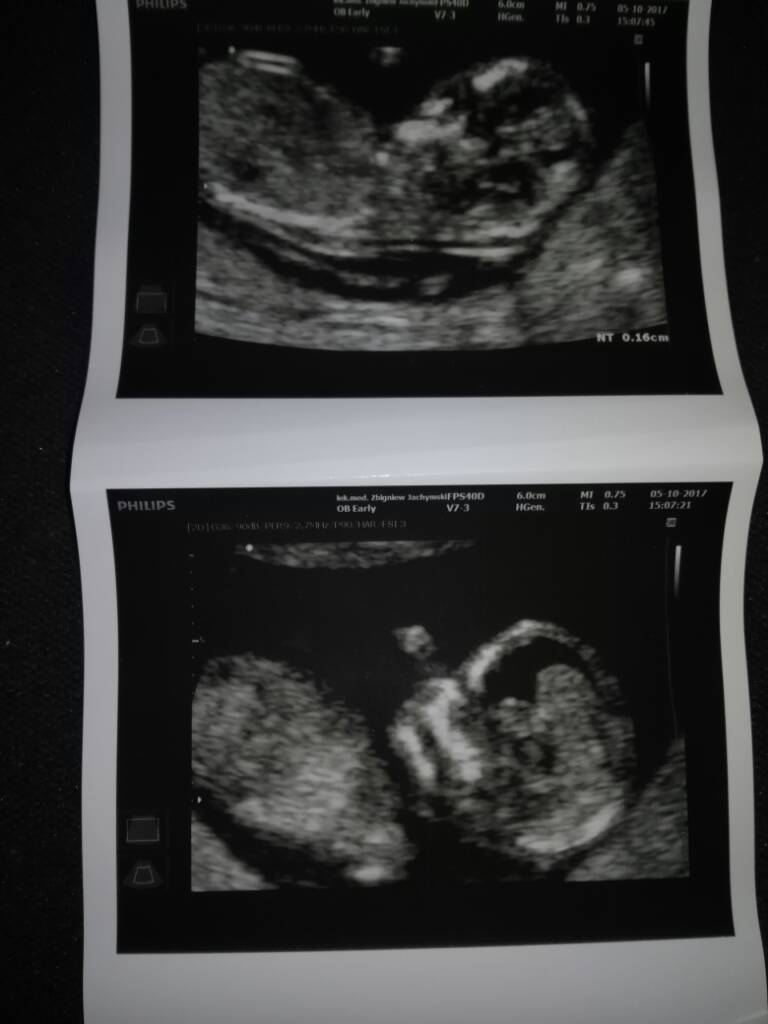

Witam.Po dłuższym podczytywaniu postanowiłam i Ja do was dołączyć:),jeśli mnie przyjmiecie oczywiście;).Na tym forum byłam ładnych pare latek temu .Czytałam was na bieżaco,ale ze wzgledu na problemy które pojawiały się od początku ciąży jakoś tak bałam się ze ledwo dołącze a bede musiała was opuścić.Teraz mam nadzieję najgorsze mieć za sobą i w końcu cieszyć się mym stanem:).Coś o mnie to mam 37 latek skończone i posiadam już św.trójce:).Dziś miałam robione usg genetyczne i wszystkko jest ok,czekam tyllko jeszcze na wynik testów pappa i też mam nadzieję ze bedą dobre :)

Ogólnie wszystko jest w normie, przeziernosc, kość nosowa, tylko maluszek ma dużo płynu w główce [emoji22]. Za 2 tyg znowu kontrola. Gin kazał narazie się nie przejmować, ale wiecie jak jest. O płeć nie pytałam bo on cały czas sprawdzał ta główkę, 40 min robił mi usg i dopochwowo i przez brzuch. Ale na koniec wizyty podczas rozmowy o tej główce powiedział mi że chłopiec. Nie wiem co myśleć, jestem załamana.

Miałam badania prenatalne. Wynik 1.5mm. To źle, Dobrze?

Wynik dobry ;)